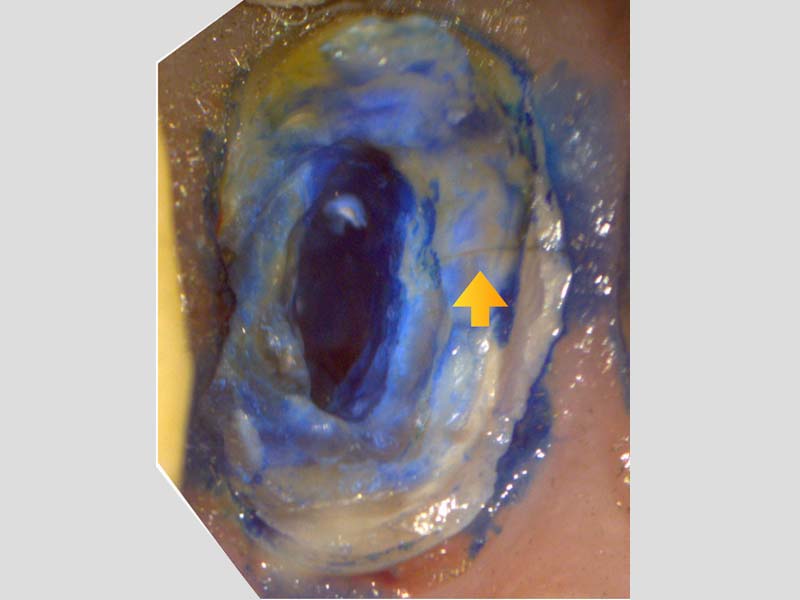

左上顎第二小臼齒:顯微鏡下確診牙裂,建議拔除

左上顎第一大臼齒:為五根管的難症(罕見變異多根根管)

左上顎第二大臼齒:也是五根管的難症(罕見變異多根根管)